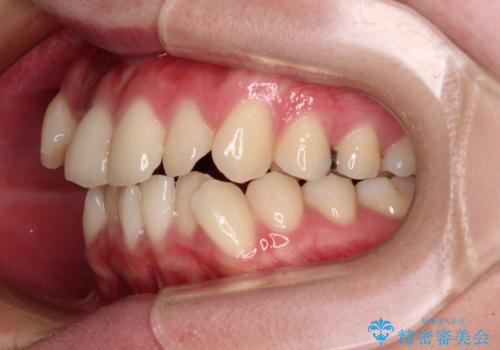

前歯のデコボコを抜歯矯正でスッキリした口元に

- 八重歯やクロスバイトを気にして来院された患者様です。

口元の突出感はありませんでしたが、デコボコが強く、非抜歯矯正とすると出っ歯仕上がりとなる可能性があったため、上下左右の第一小臼歯4本を抜歯し、ワイヤー装置にて矯正治療を行うこととしました。

デコボコがスッキリするだけでなく、口元の突出感も少し改善され、満足のいく仕上がりとなりました。